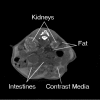

Figure 5

Kidney scan of an adult mouse acquired using 250 ml i.p. injected Nycomed Omnipaque 300 contrast media to enhance the CT Numbers of the kidneys and peritoneal fluids.